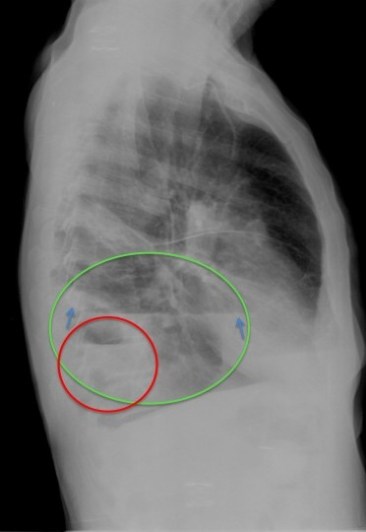

CASO: Febrícula y tos de 4 días de evolución.

Hallazgos:

- En la placa PA se observa una asimetría en los hilios pulmonares, el hilio izquierdo tiene una densidad aumentada.

- Tras examinar la placa lateral se observa un aumento de densidad en la columna que puede ser compatible con una condensación, es el signo de la desnificación vertebral.

SIGNO DE LA DENSIFICACIÓN VERTEBRAL: En la radiografía lateral normal, la densidad de la columna torácica tiende a disminuir desde la parte superior hasta el diafragma; la alteración de ese patrón por la presencia de una densidad superpuesta a la columna, indica la existencia de una consolidación pulmonar. Este signo adquiere especial valor cuando en la proyección posteroanterior la consolidación está oculta en el espacio retrocardíaco o en la base pulmonar.